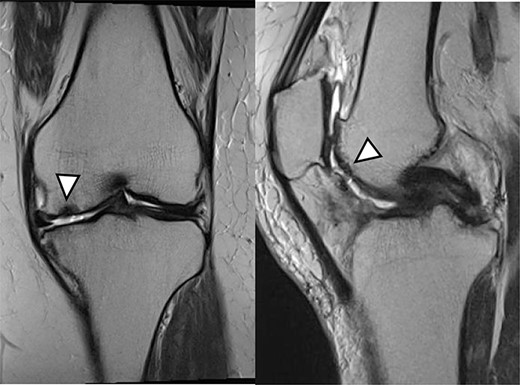

There were cartilage defects (arrowhead) in the medial femoral condyle and trochlea of the left knee (a, b).

A 42-year-old female (BMI, 27.4 kg/m2) presented with 2 years of left knee medial joint pain. Active range of motion (ROM) in the left knee was from 0 to 140 degrees with no extension lag. Preoperative Tegner scores, Lysholm scores and Knee Injury and Osteoarthritis Outcome (KOOS) scores are shown in Table 1. Preoperative radiographs of the left knee joint showed mild medial osteoarthritis (OA) of the knee and hip–knee–ankle (HKA) angle of 1.5-degree varus. 1.5-Tesla MRI was performed on unit (Toshiba, Kawasaki, Japan) was used with an extremity surface coil. Proton density images were obtained using the fast spin-echo technique. A modified magnetic resonance observation of cartilage repair tissue (MOCART) system was used for the quantitative evaluation of MRI findings of the cartilage injury [15–17]. MRI showed cartilage injury of the medial femoral condyle (MFC) and trochlea of the left knee (Fig. 1).

MRI showed cartilage injury of the medial femoral condyle (arrowhead).